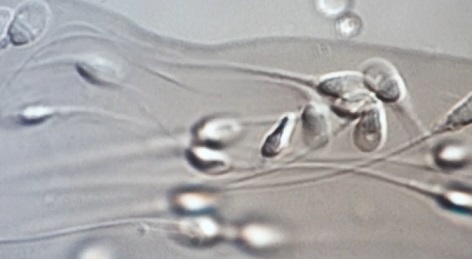

정자·난자와 같은 생식 세포는 생물학적 나이가 들수록 가임력이 떨어진다.

남성 난임 원인 1위, 정계정맥류

파란 눈의 요리사로 잘 알려진 미카엘 아쉬미노프(43) 씨는 작년 골반 부위 통증이 심해지면서 병원을 찾았고 남성 난임의 원인으로 알려진 ‘정계정맥류’라는 예상치 못한 진단을 받았다.

지난 2월 수술 후 정자 수와 질에 있어서 눈에 띄는 변화가 포착됐다.